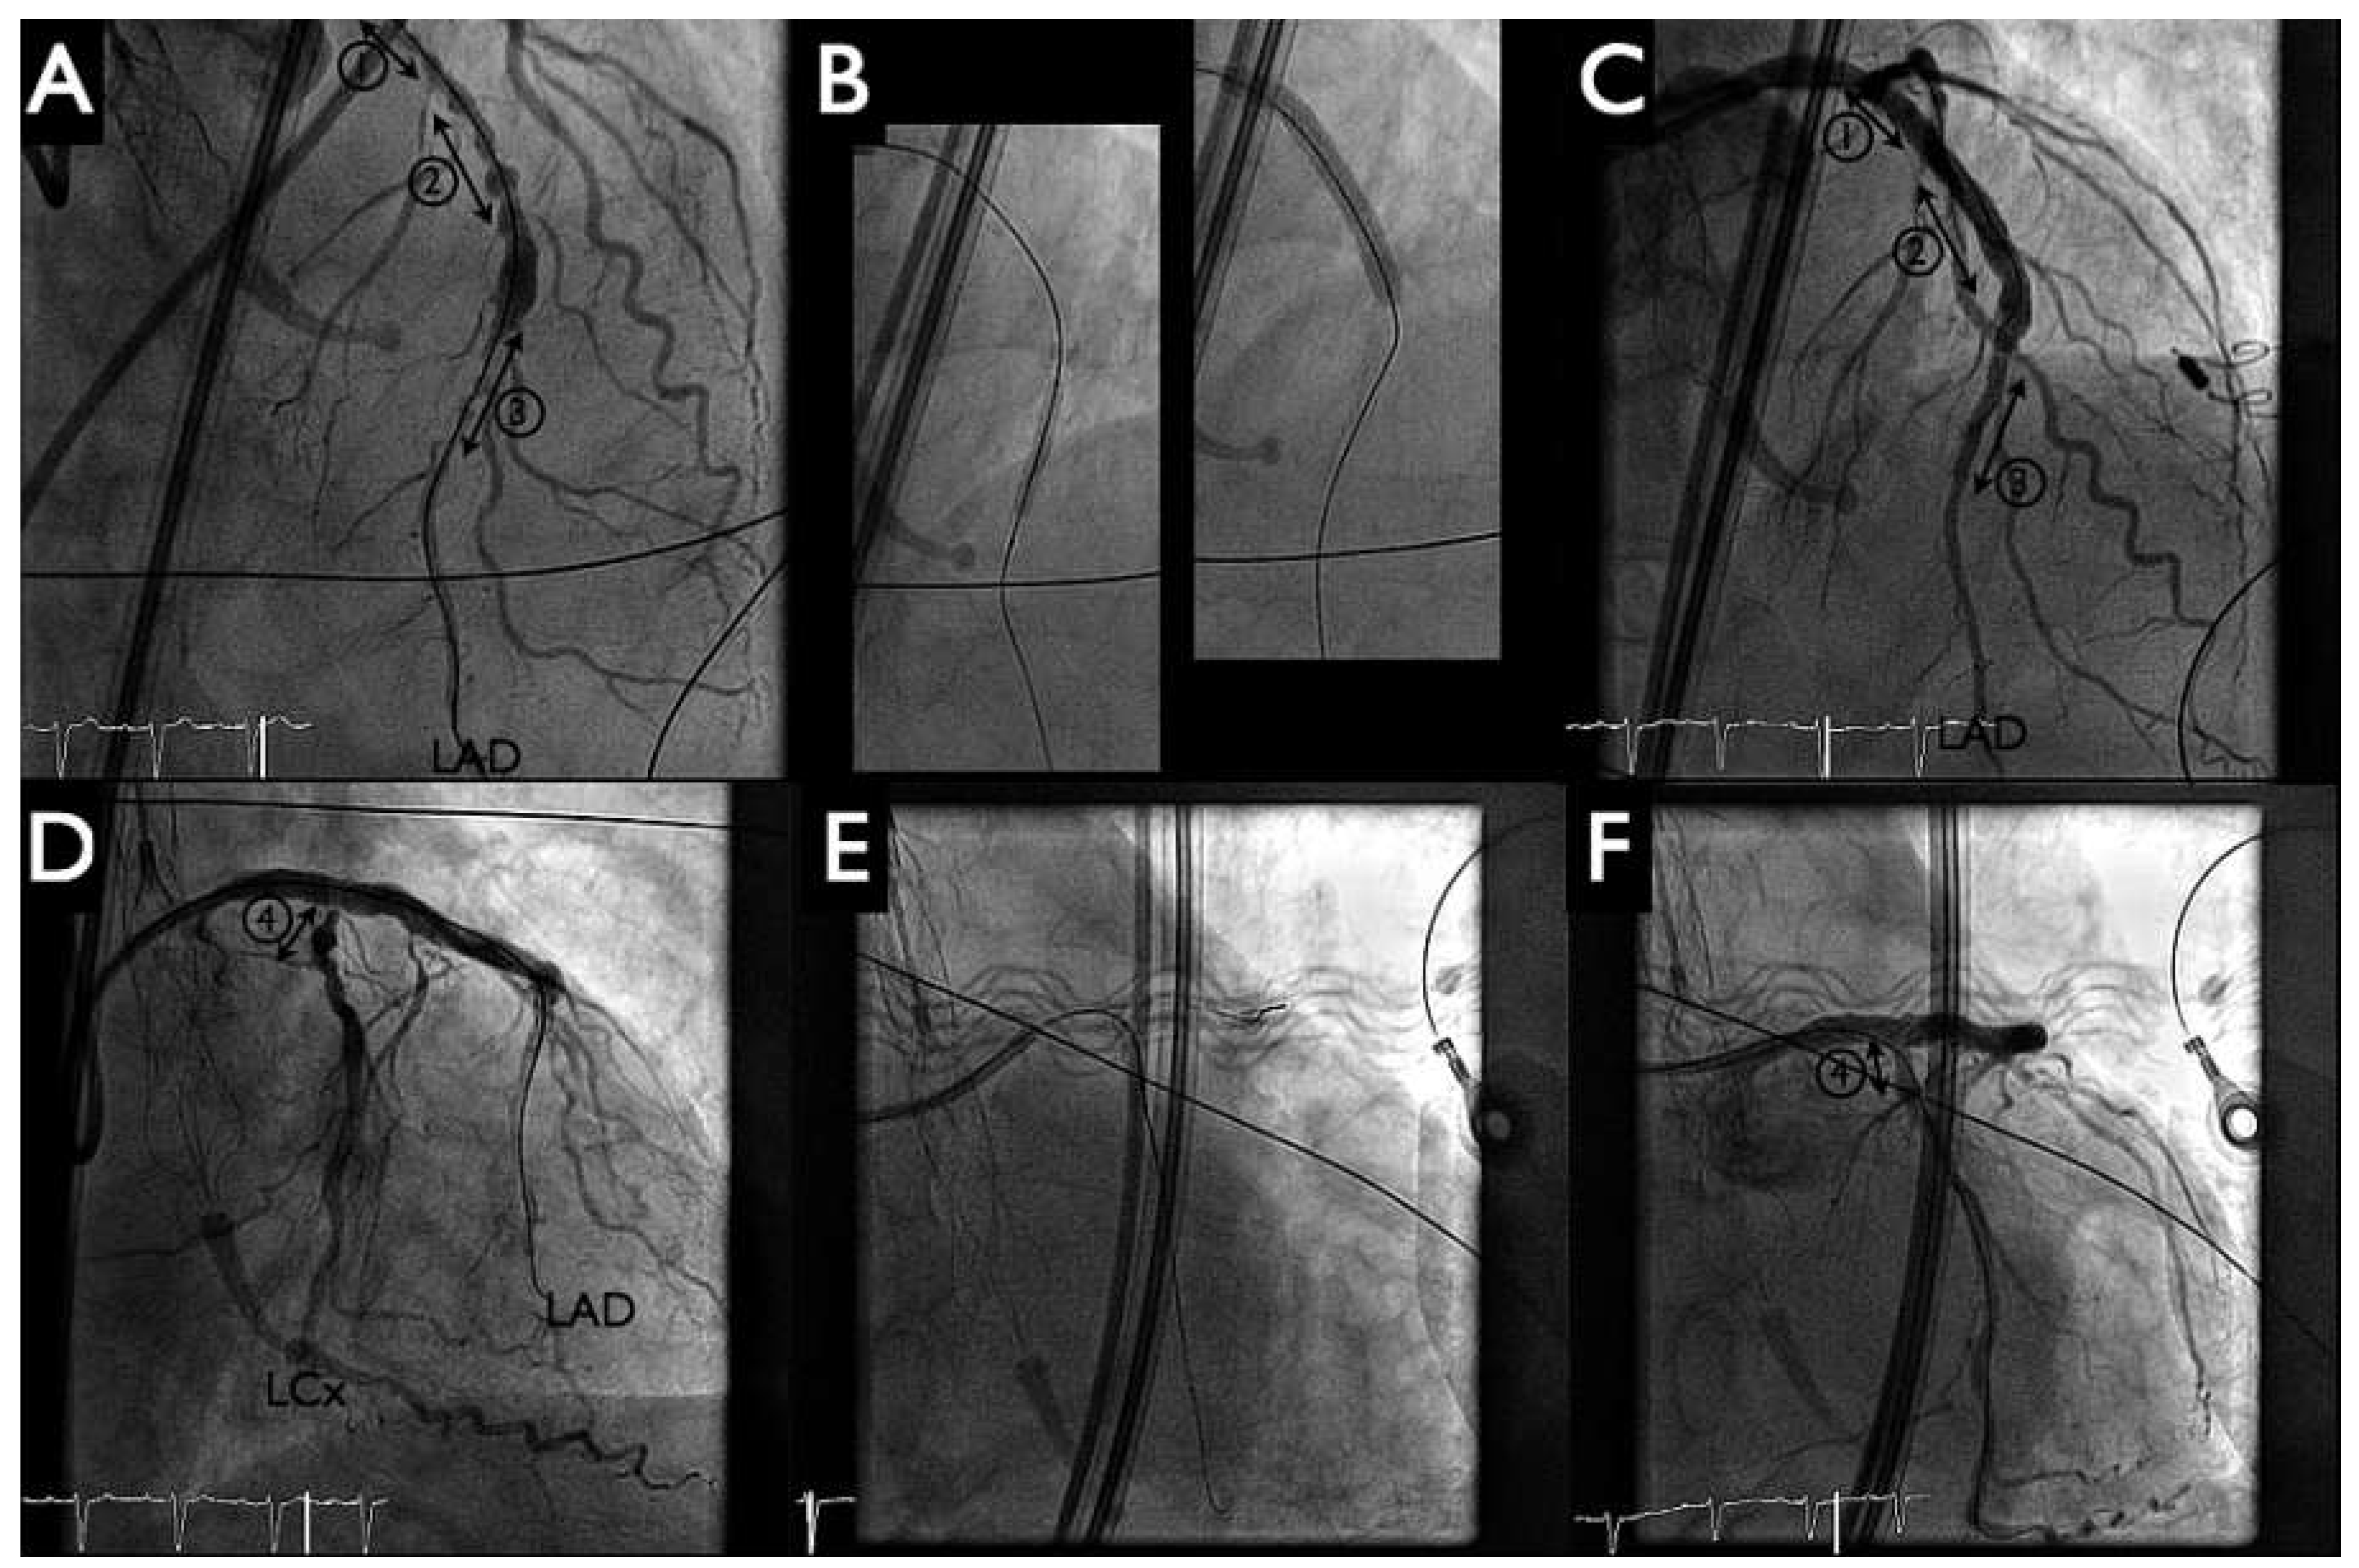

Figure 2. Coronary angiograms (panels A–D) and left ventricular angiogram (panels E, F). Three-vessel coronary artery disease with subtotal distal left main (3) to proximal left anterior descending artery (LAD) stenosis (lesion 1), significant proximal (lesion 2) and distal (lesion 3) LAD stenosis, high grade ostial circumflex artery (LCx, lesion 4), and intermediate lesions from the mid portions of LCx and the right coronary artery (RCA). Left ventricular ejection fraction was severely depressed (panels E, F).

An otherwise active and independent 86-year-old male with a history of poorly controlled hypertension consulted for progressive shortness of breath and typical angina Canadian Cardiovascular Society (CCS) class III. His ECG showed first degree atrioventricular block, a left anterior hemiblock and Q waves from V1–V4. There was left ventricular hypertrophy with severe systolic dysfunction (left ventricular ejection fratction [LVEF] 30%) and anterior wall hypokinesis, but no significant valvular disease on echocardiogram (left ventricular angiogram, Figure 2 panels E, F). The coronary angiogram revealed severe three-vessel coronary artery disease (Figure 2 panels A–D). There was a significant stenosis of the distal left main (Medina 1.1.1). The left anterior descending artery was suboccluded in the proximal and distal portion with numerous calcified and aneurysmal lesions. The proximal, middle and distal circumflex artery, as well as the mid portion of the right coronary artery, had significant stenosis.